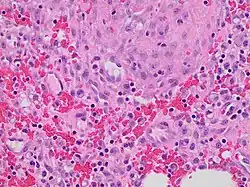

Granulation tissue is new connective tissue and microscopic blood vessels that form on the surfaces of a wound during the healing process.[1] Granulation tissue typically grows from the base of a wound and is able to fill wounds of almost any size. Examples of granulation tissue can be seen in pyogenic granulomas and pulp polyps. Its histological appearance is characterized by proliferation of fibroblasts and thin-walled, delicate capillaries (angiogenesis), and infiltrated inflammatory cells in a loose extracellular matrix.

The main immune cells active in the tissue are macrophages and neutrophils, although other leukocytes are also present.[6] These work to phagocytize old or damaged tissue, and protect the healing tissue from pathogenic infection. This is necessary both to aid the healing process and to protect against invading pathogens, as the wound often does not have an effective skin barrier to act as a first line of defense.

It is necessary for a network of blood vessels to be established as soon as possible to provide the growing tissue with nutrients, to take away cellular wastes, and transport new leukocytes to the area. Fibroblasts, the main cells that deposit granulation tissue, depend on oxygen to proliferate and lay down the new extracellular matrix.[7]

In vascularisation, also called angiogenesis, endothelial cells quickly grow into the tissue from older, intact blood vessels.[8] These branch out in a systematic way, forming anastomoses with other vessels.